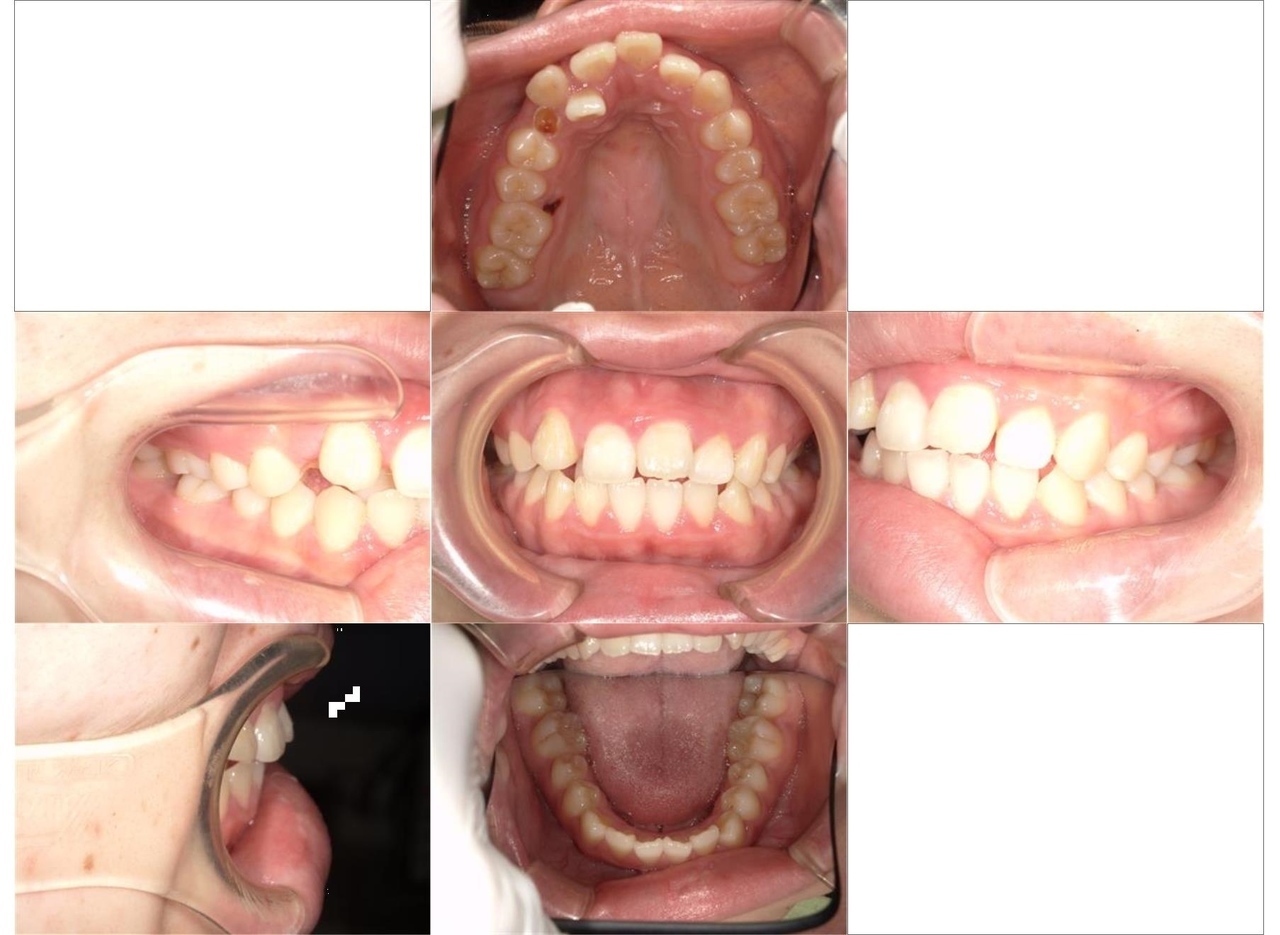

はじめに、乳歯の抜歯を行い、乳歯を抜歯したスペースに永久歯を配列しました。また、舌側に位置していた永久歯も上顎の歯列に配列しました。全体の歯の配列が整ってきたので、顎間ゴムにて咬合の緊密化を行い、矯正治療を終了しました

マルチブラケット装置による矯正治療は、歯の三次元的な動きが可能であることから、歯科矯正治療においては、とても効果の高い治療法であると考えています。

術後の経過

現在は、メンテナンス中